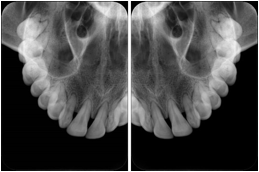

3. A dental provider wishes to capture a series of DICOM IO images for the patient’s dentition. The tooth morphology, teeth are divided into molars, premolars, canines and incisors, and a number of images for each jaw. The anatomic information was captured utilizing the triplet of schema. This standard code sequence is based on ISO 3950-2010, Dentistry - Designation system for teeth and areas of the oral cavity.

Every IO image should have anatomic information either through the primary or modifier sequence.

In most standard cases, images are oriented in structured layouts. These structured displays are useful to be shared between providers for reference purposes.

Table OO.1.1-1 shows structured display standard templates, where Viewset ID is based on the Japanese Society for Oral and Maxillofacial Radiology (JSOMR) classification provided by JIRA (Japan Medical Imaging and Radiological Systems Industries Association, www.jira-net.or.jp). Expected or typical teeth to be imaged location, region and designation codes are based on ISO 3950-2010, Dentistry - Designation system for teeth and areas of the oral cavity. For all the hanging protocols listed in OO.1.1-1, the value to use for Hanging Protocol Creator (0072,0008) is "JSOMR" and the value to use for Hanging Protocol Name (0072,0002) does not include "JSOMR" (e.g., "DL-S001A", not "JSOMR DL-S001A").